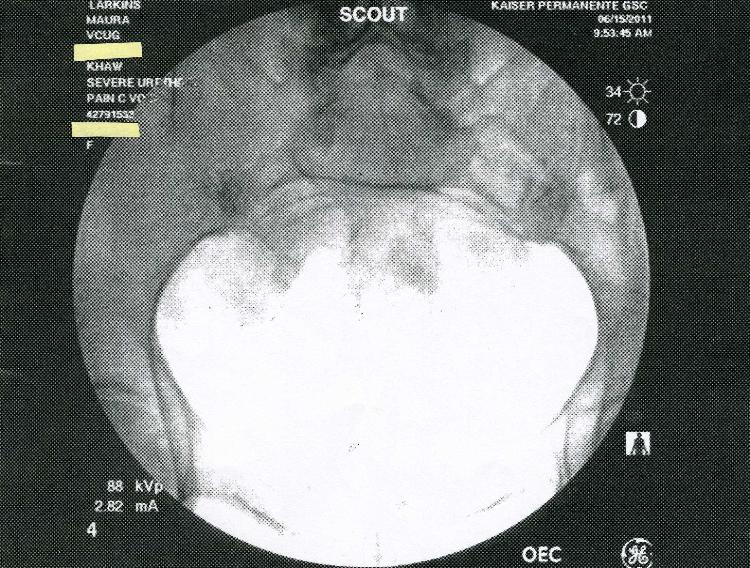

In July 2011 Kaiser Permanente in San Diego claimed that a large series of

X-rays done at the brand new Garfiled Specialty Center was not preserved on

film or saved electronically.  Kaiser claimed that only five images were

saved-on thermal paper! Below are the five images.  Incredibly, two of the

saved images are previews, or "scout" x-rays.  Why would these be printed

out?  They were not medically useful.  Answer: The truth is that all the images

were saved digitally, and Kaiser concealed them to cover-up an incorrect

diagnosis.